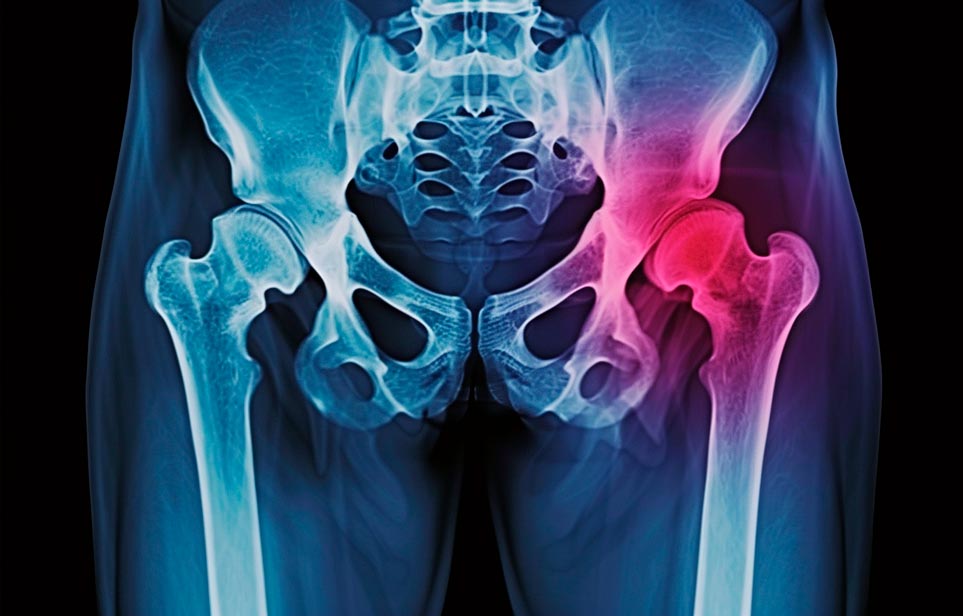

Реабилитация пожилых после перелома шейки бедра в Челябинске

Эффективная и профессиональная реабилитация после перелома шейки бедра в Челябинске осуществляется по демократичным ценам лучшими специалистами современной медицинской клиники «Заботливые люди» с применением персонального подхода к каждому пожилому человеку с такой тяжёлой травмой бедренной кости ноги. В процессе осуществления такой специализированной услуги все наши пациенты имеют возможность получения качественного и достойного обслуживания, эффективного восстановления. Лучший дом престарелых позаботиться о Вашем близком человеке.

Такая травма в большей части случаев возникает у граждан преклонного возраста. При её появлении на протяжении длительного времени сохраняются болевые и неприятные ощущения в области паха, при которых серьёзно ухудшается качество жизни, возникает множество последствий для его жизни и здоровья.

По какой симптоматике можно определить перелом шейки бедра

- Визуально повреждённая нога сокращается на несколько сантиметром из-за сокращения мышц.

- Стопа выворачивается наружу.

- В лежачем положении человек не может поднять ногу.

При такой симптоматике важно незамедлительно обращаться к специалистам для получения всей необходимой помощи, терапии и восстановления после перелома шейки бедра. Если не оказать помощи старику, то это приведёт к гноению, инвалидности, иным видам осложнений.